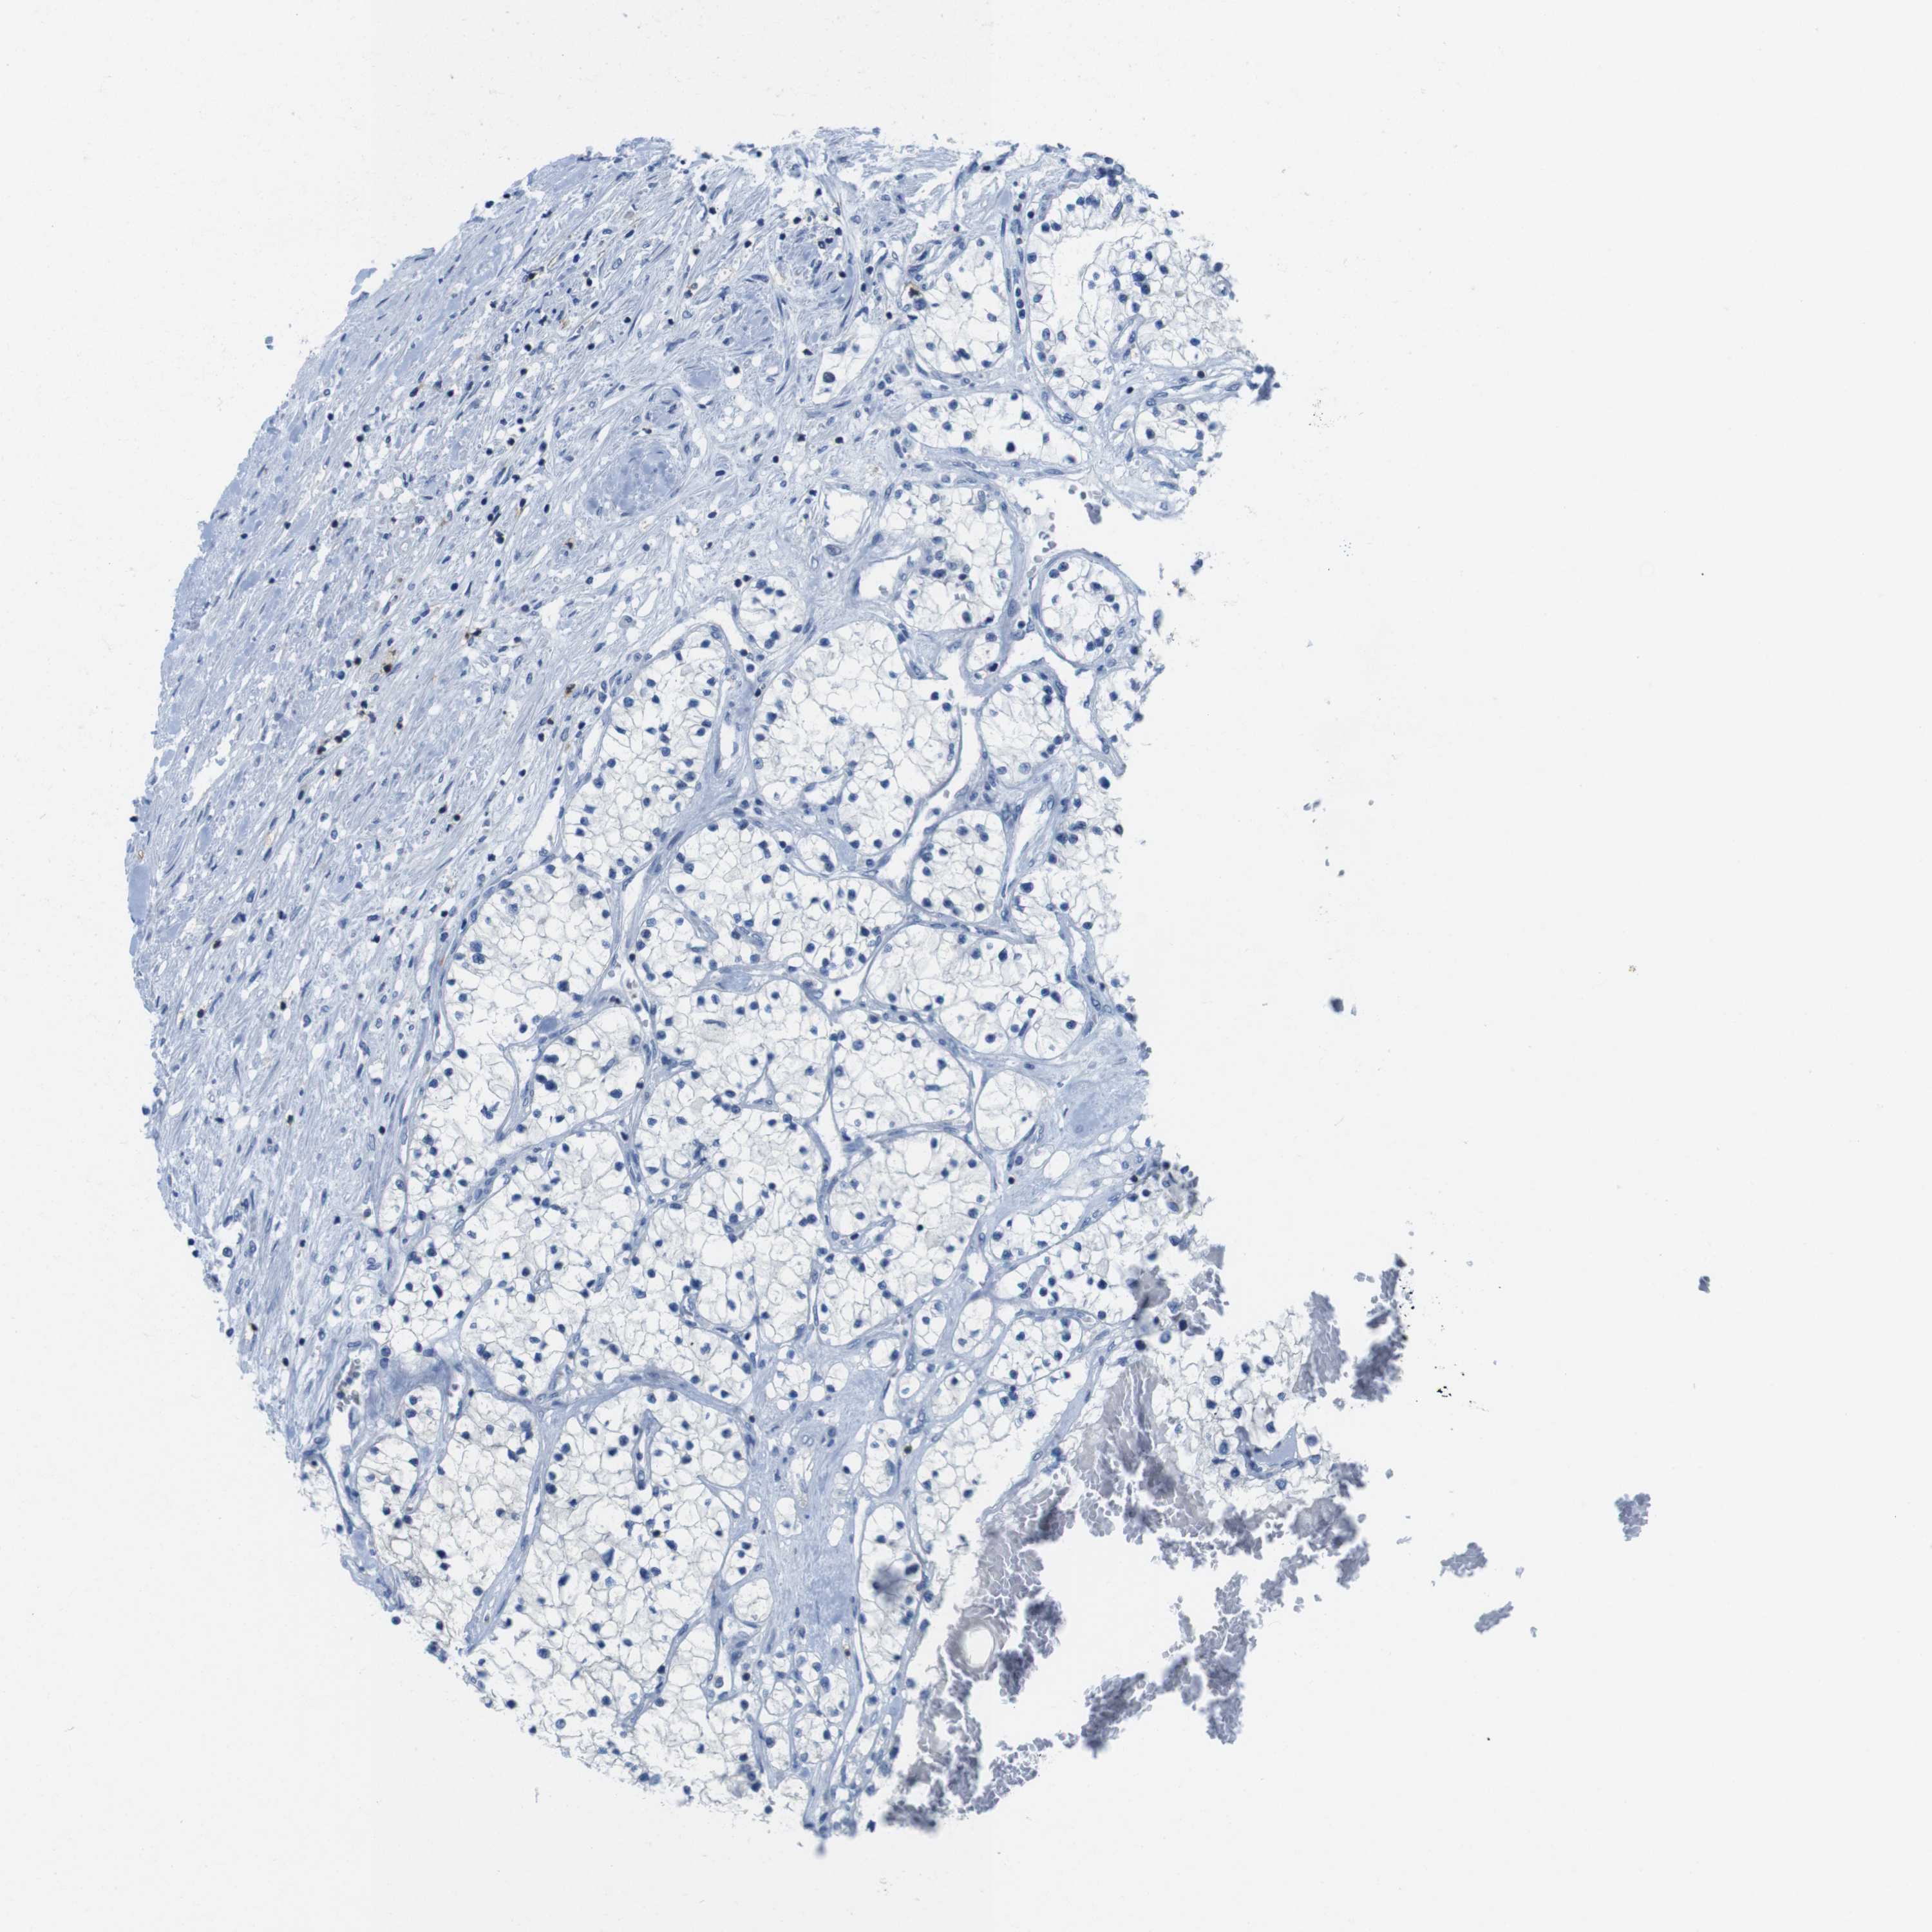

KIDNEY RENAL CLEAR CELL CARCINOMA (TCGA) - Interactive survival scatter ploti

CD5 is not prognostic in Kidney Renal Clear Cell Carcinoma (TCGA)

Average pTPM 4.0

Number of samples 521